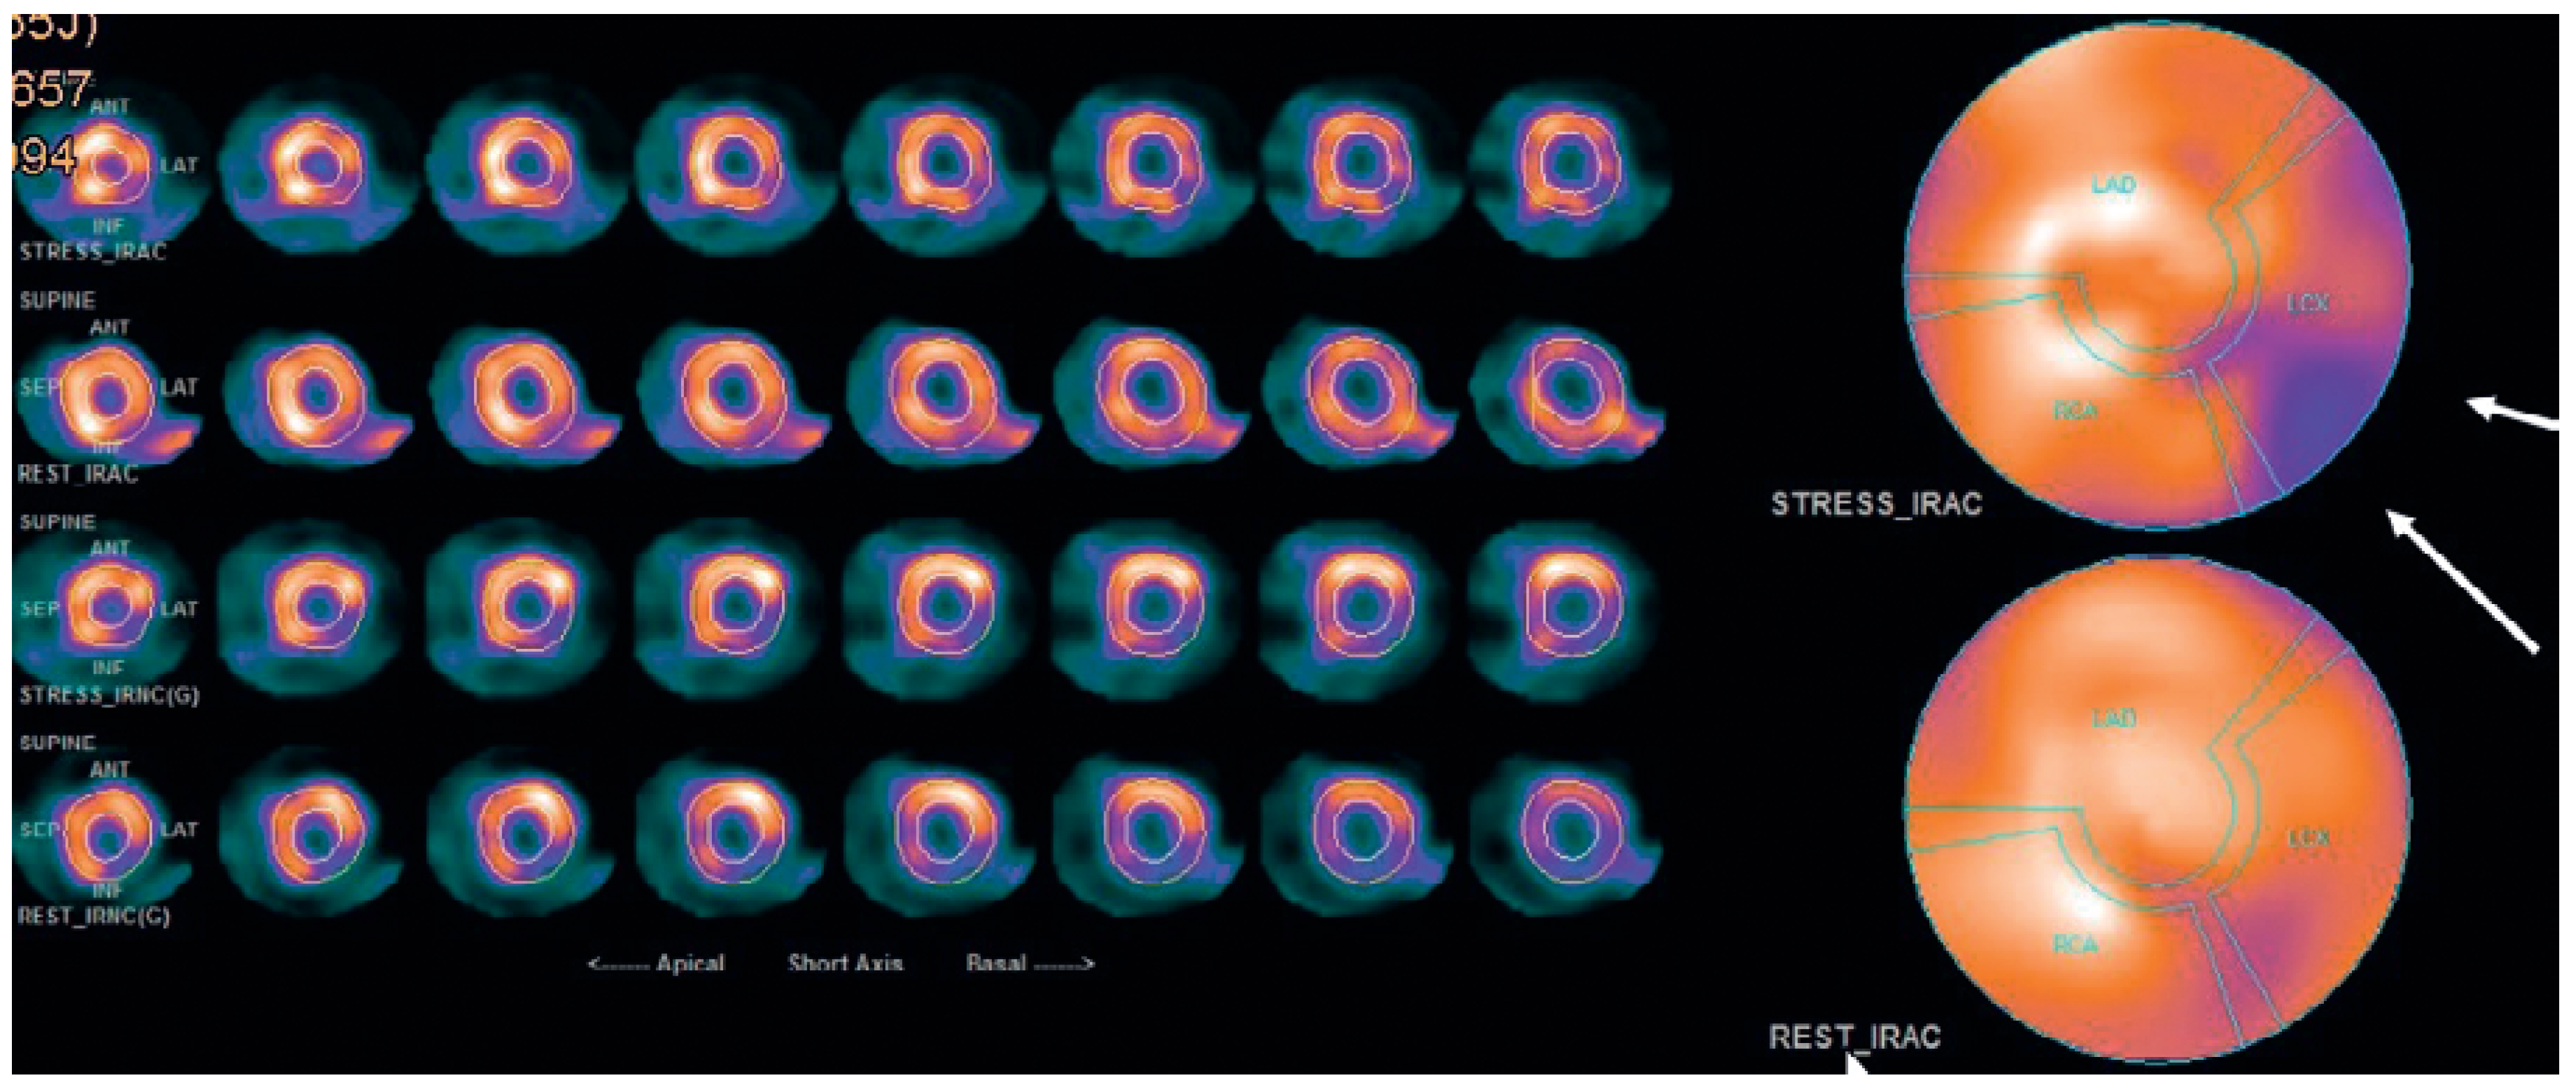

To exclude coronary artery disease the patient was referred for a cardiac single photon emission computed tomography (SPECT) scan using technetium-99m, which revealed a normal radionuclide tissue distribution at rest, but after physical stress using a bicycle ergometer significant left ventricular inferior-lateral ischaemia of 10–15% was observed (Figure 2). Elective coronary angiography confirmed coronary artery disease with chronic total obstruction of the left circumflex artery. One drug-eluting stent was placed successfully (Figure 3).

Figure 2. Single-photon emission computed tomography (SPECT); arrows indicate ischaemia in the area supplied by the left circumflex artery.